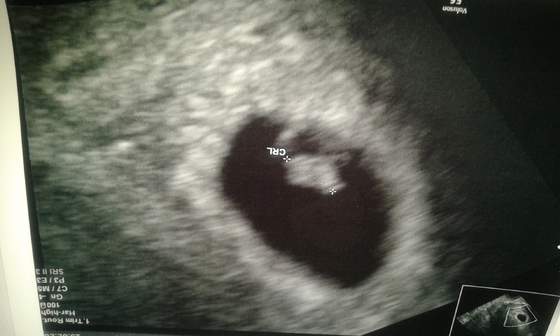

Dzidziusiowe USG :)

ImageUploadedByForum BabyBoom1409249278.906780.jpg Nasz Aniołek ma 7 tyg. I 1 dzień i bije Mu serduszko :)